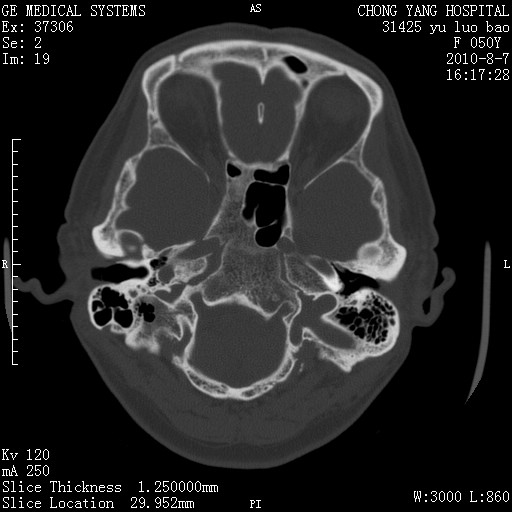

标题: CT28285:听力下降一年,头昏。 [打印本页]

标题: CT28285:听力下降一年,头昏。

骨窗示右侧内听道扩大,考虑右侧听神经瘤。

右侧桥小脑角区等密度占位,内耳道扩大,听神经瘤